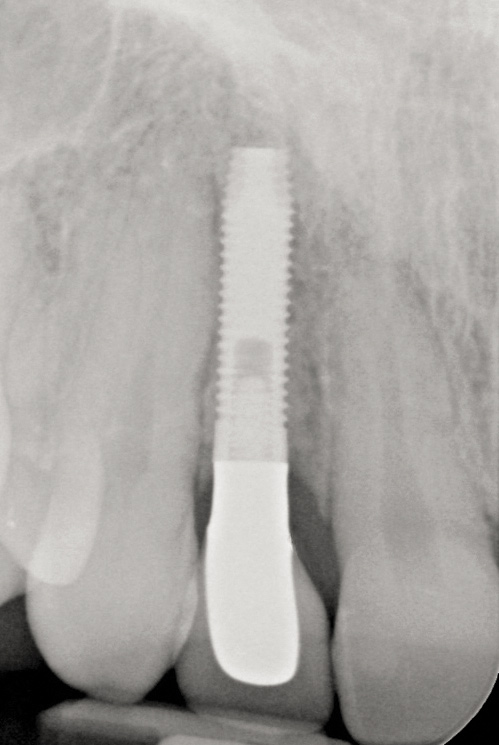

Fig 17. Radiograph showed symmetrical infrabony defect affecting 50% of the implant surface.

Figure 17

Clinical examination showed 2 mm of buccal recession with a shallow vestibule and absence of keratinized attached gingiva against the crown with 8 mm of circumferential pocketing accompanied by bleeding upon probing (Figure 15 and Figure 16). A periapical radiograph showed a symmetrical vertical osseous defect causing the loss of 50% of the bone around the implant (Figure 17). Because the patient had made a significant investment of time and finances to replace her lost tooth with the implant, she desired that the implant and restoration be retained, if feasible.